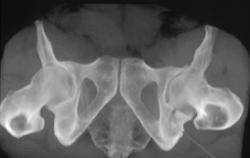

Scapular Fracture